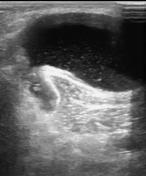

Hình ảnh siêu âm, MRI